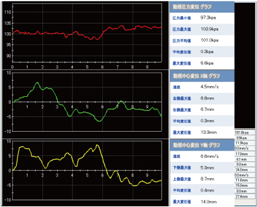

歩行検査

片方ずつの足でプレートを踏んで歩行し検査します。

圧力中心線の軌跡や歩行周期を動画で記録できます。

計測画面

足長、足幅、角度の計測が行えます。圧力中心線の軌跡から回内足、回外足等の歩行異常の分析が行えます。

フレーム分布

歩行時の接地状態を0.06秒毎のコマ送りにしたデータです。左右のフレーム数の違いから被験者へ荷重時間の差を視覚的に説明する事が出来ます。

グラフ

重心線の軌跡をグラフ化し分析します。